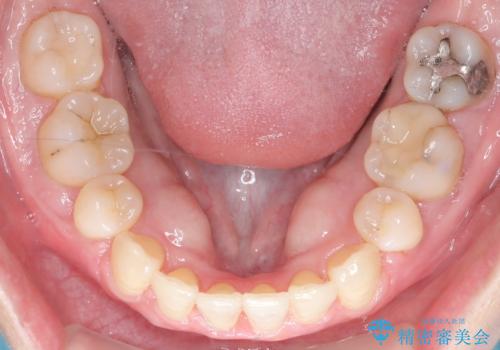

前歯が前に出ていることや歯並びの凸凹が気になるという主訴でした。十分なスペースを確保するため上下左右の第一小臼歯(4番)を抜歯し、そこに前歯を移動させて整列を行いました。矯正装置には目立ちにくい透明なブラケットを選択し、見た目のストレスを軽減。矯正期間中は定期的な通院でワイヤーを微調整し、無理なく確実に歯を動かしました。治療後は前歯が自然な位置に下がり、口元の突出感が解消されるとともに、美しく整った口元に仕上がり、患者様にも大変喜んでいただけました。